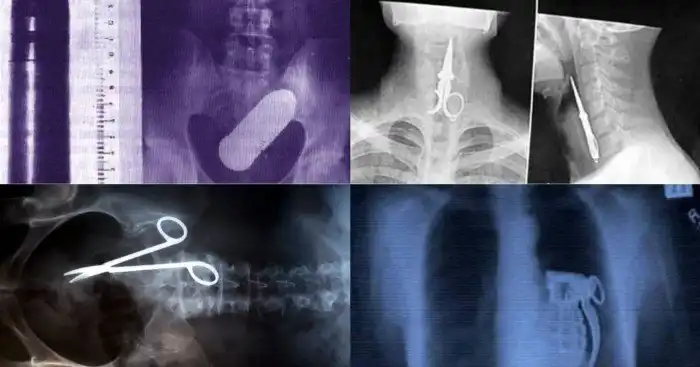

Интересно, как врачи умудряются забыть инструмент, внутри тела пациента?

И снова о ножницах. Это человек пытался использовать их как зубочистку. Вышло, как видите, неудачно.

Обычно лампочки, ради интереса, засовывают в рот. Здесь же интерес, видимо, выдался другим.